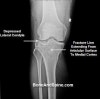

X-ray : 경골 고평부 골절(Tibial plateau fracture)

무릎의 AP & lateral view 외에 oblique view를 시행합니다.

3D-CT검사가 놓치지 쉬운 골절이나 함몰을 확인하는데 도움이 됩니다.